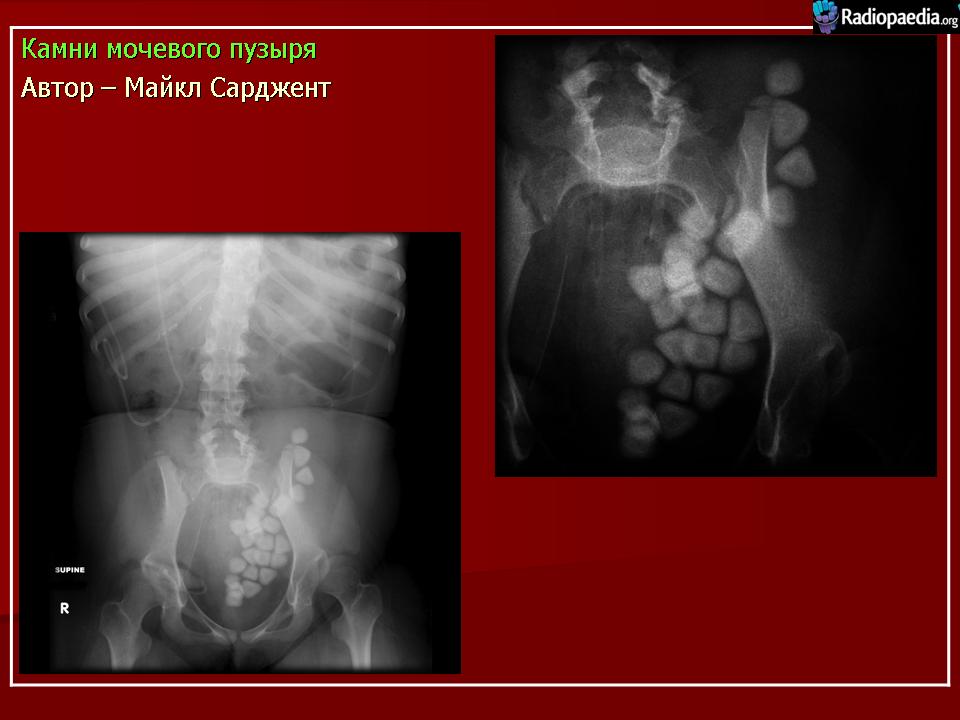

Дайте заключение по данному снимку// доброкачественное новообразование мочевого пузыря// +Камни мочевого пузыря// Инородные тела мочевого пузыря// Множественные полипы мочевого пузыря// Злокачественное новообразование мочевого пузыря